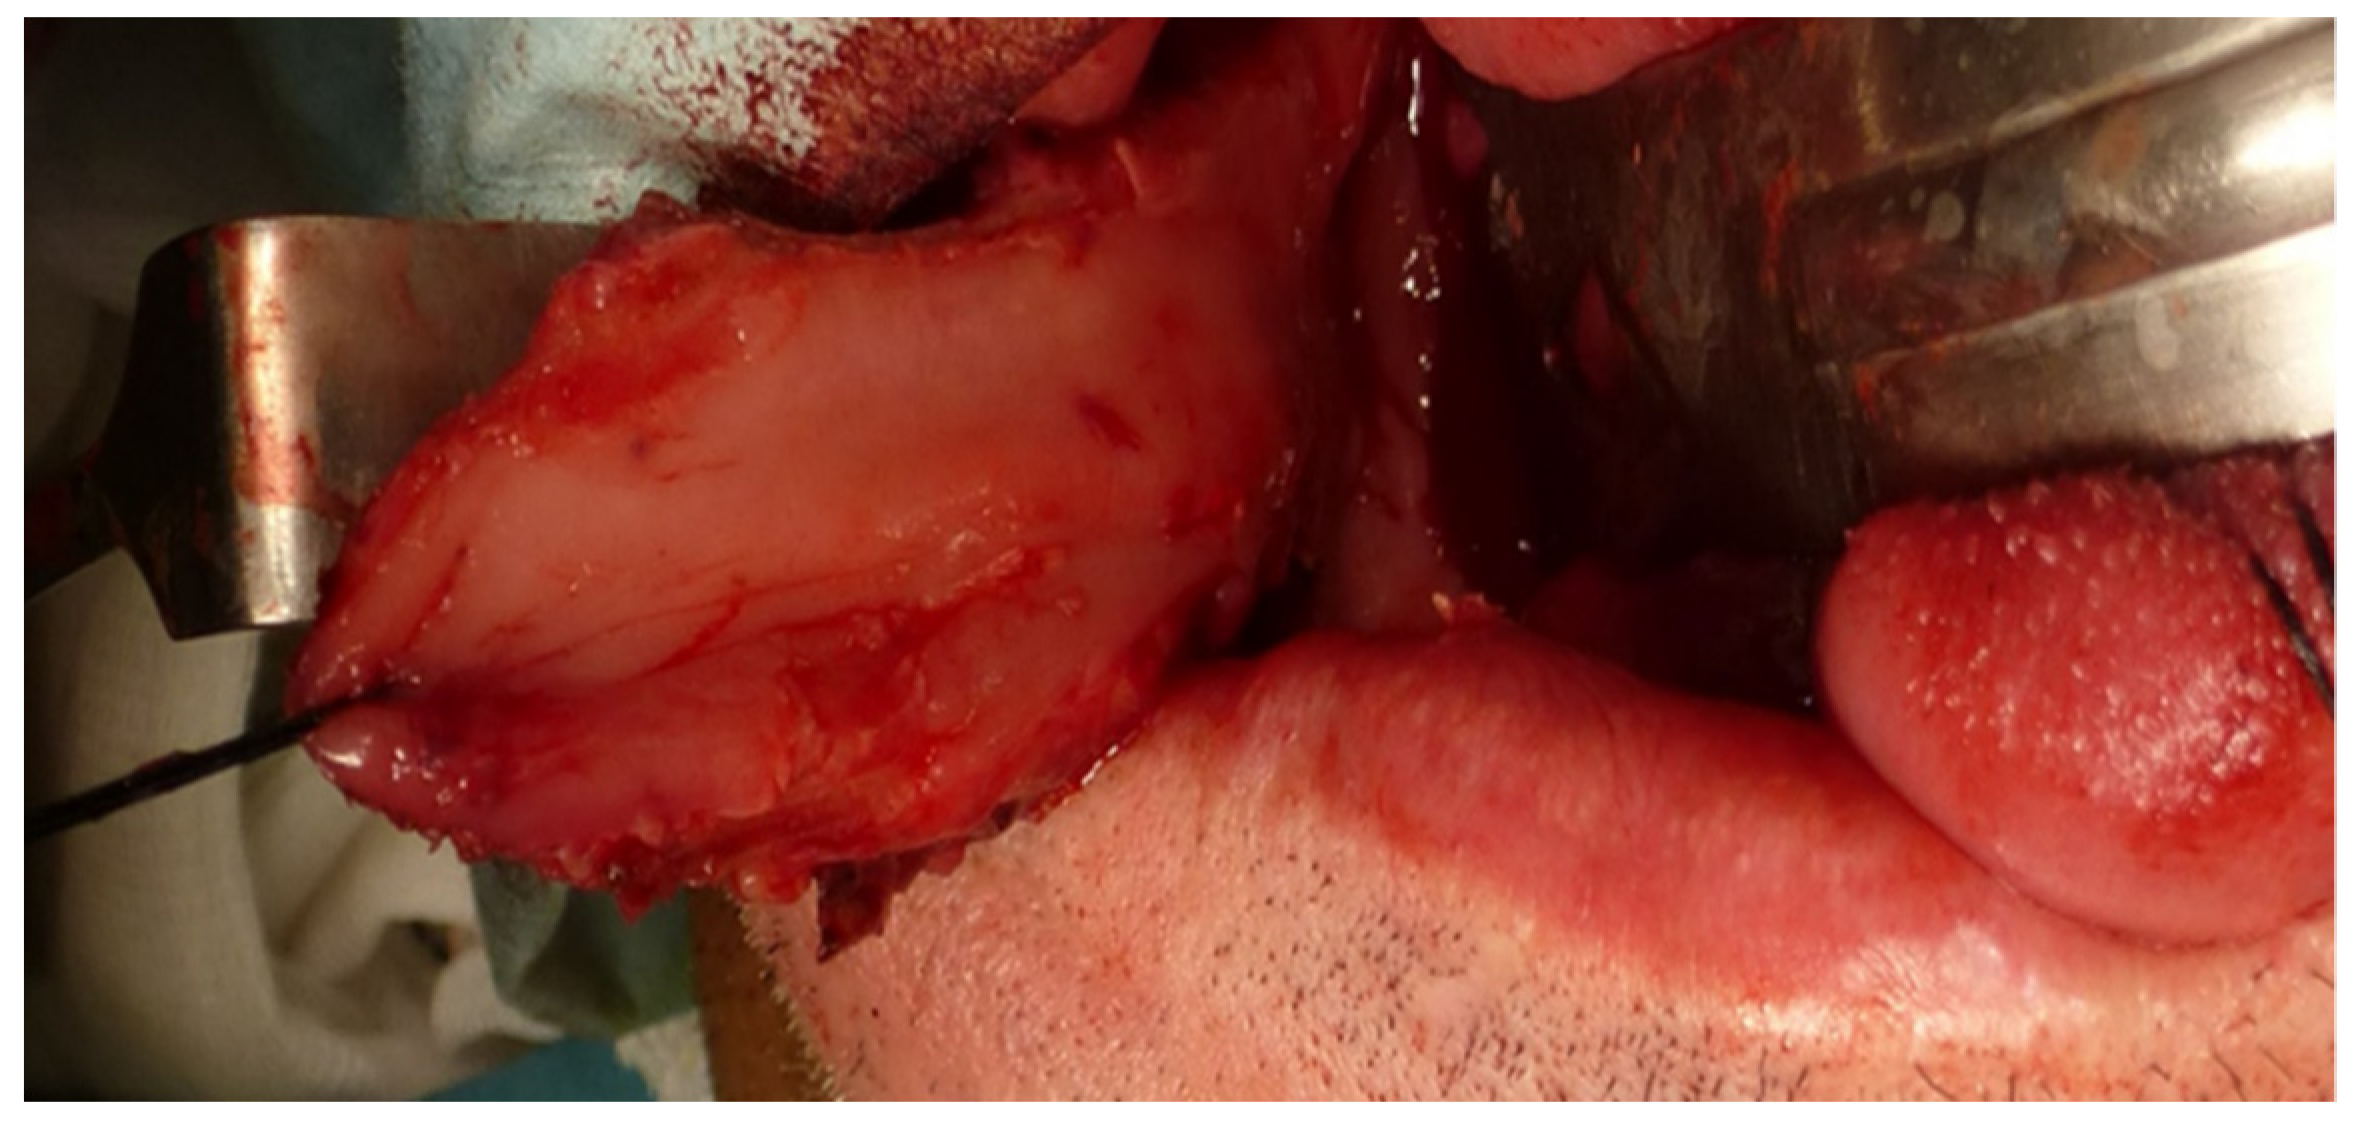

A homolateral selective cervical dissection with resection of the tumor of the tongue and floor of the mouth with free margins was performed. The defect to be reconstructed was 5.7 × 3.6 cm and a FAMM flap was designed for reconstruction (Figure 2).

Immediate reconstruction of the defect was performed with an inferiorly based FAMM flap (Figure 3 and Figure 4) and immediate placement of 12 dental implants, 6 in the mandible and 6 in the maxilla (Figure 5). There were no postoperative complications, and the patient received postoperative radiotherapy (60 Gy). Eight months later, prosthetic rehabilitation of the dental implants was performed, and the aesthetic and functional evaluations were accomplished.

Figure 3. Right FAMM flap inferiorly pedicled with an anterograde flow on the facial artery.